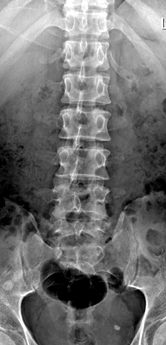

主诉:腰部疼痛1年余,伴左下肢疼痛麻木3月。 病史:女性患者,53岁。患者1年余前在做家务时出现腰部剧烈疼痛,当时腰部活动受限,在外院门诊诊断为腰肌劳损,给予对症治疗,效果较好。1年余来活动后腰部均出现疼痛,反复出现。最近3年以来,患者腰部疼痛时间延长,加重,并伴左下肢麻木,放射痛至足踝处。患者一般情况尚可。

查体:腰4/5、腰5/骶1棘间及左右棘旁轻压痛、叩击痛,左侧坐骨神经出口处明显压痛。左小腿外侧感觉略减退,左侧伸膝、踇背伸肌力4级,左侧直腿抬高试验20°(+),加强(+),Lasegue征(+),左侧4字征(+),左侧股神经牵拉试验(+)。双侧Babinski 征及Oppenheim 征(-)。 辅助检查:三大常规、血生化、肝肾功能均未见明显异常。患者腰椎动力位片正常,其余重要腰椎影像学如下。

诊断:腰椎间盘突出症(L4/5) 治疗:患者入院后尽快完善相关检查,患者目前腰椎稳定性尚可,暂拟”椎间孔镜微创“治疗。